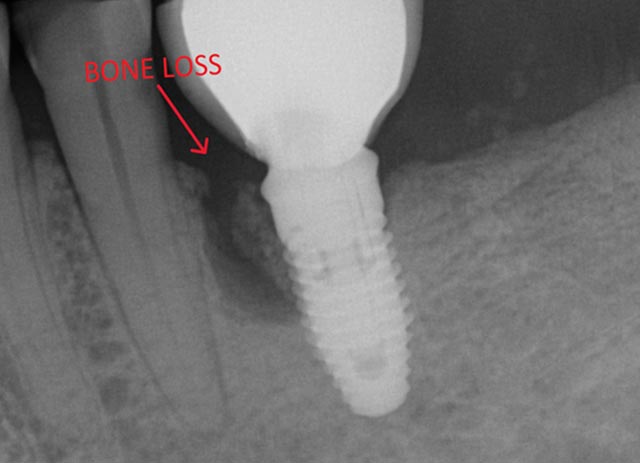

Implant Bone Grafting - Before And After

Implant bone grafting – before surgery

Implant bone grafting – after surgery